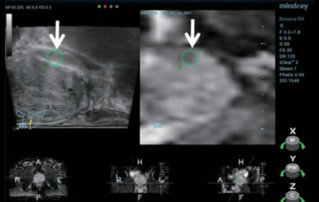

?? ? ???????? ?? ?? ??? ??? ???? ???? ?? ?? ??? ????. ????? ?????? ???? CUDI(??? ???? ??) ? ??? ??? ???? ? ??? ??? ? ?? ???, CUDI, ???(pessary)? ??? ?? ???(???? ??? ???? ? ? 7? ??). ?? ??? 3D ??? ? ?? ??? ??? ??? ?? ??? ?? ???? ??? ?? ?? ??? ????? ???? ?? ??? ??? ??? ????.